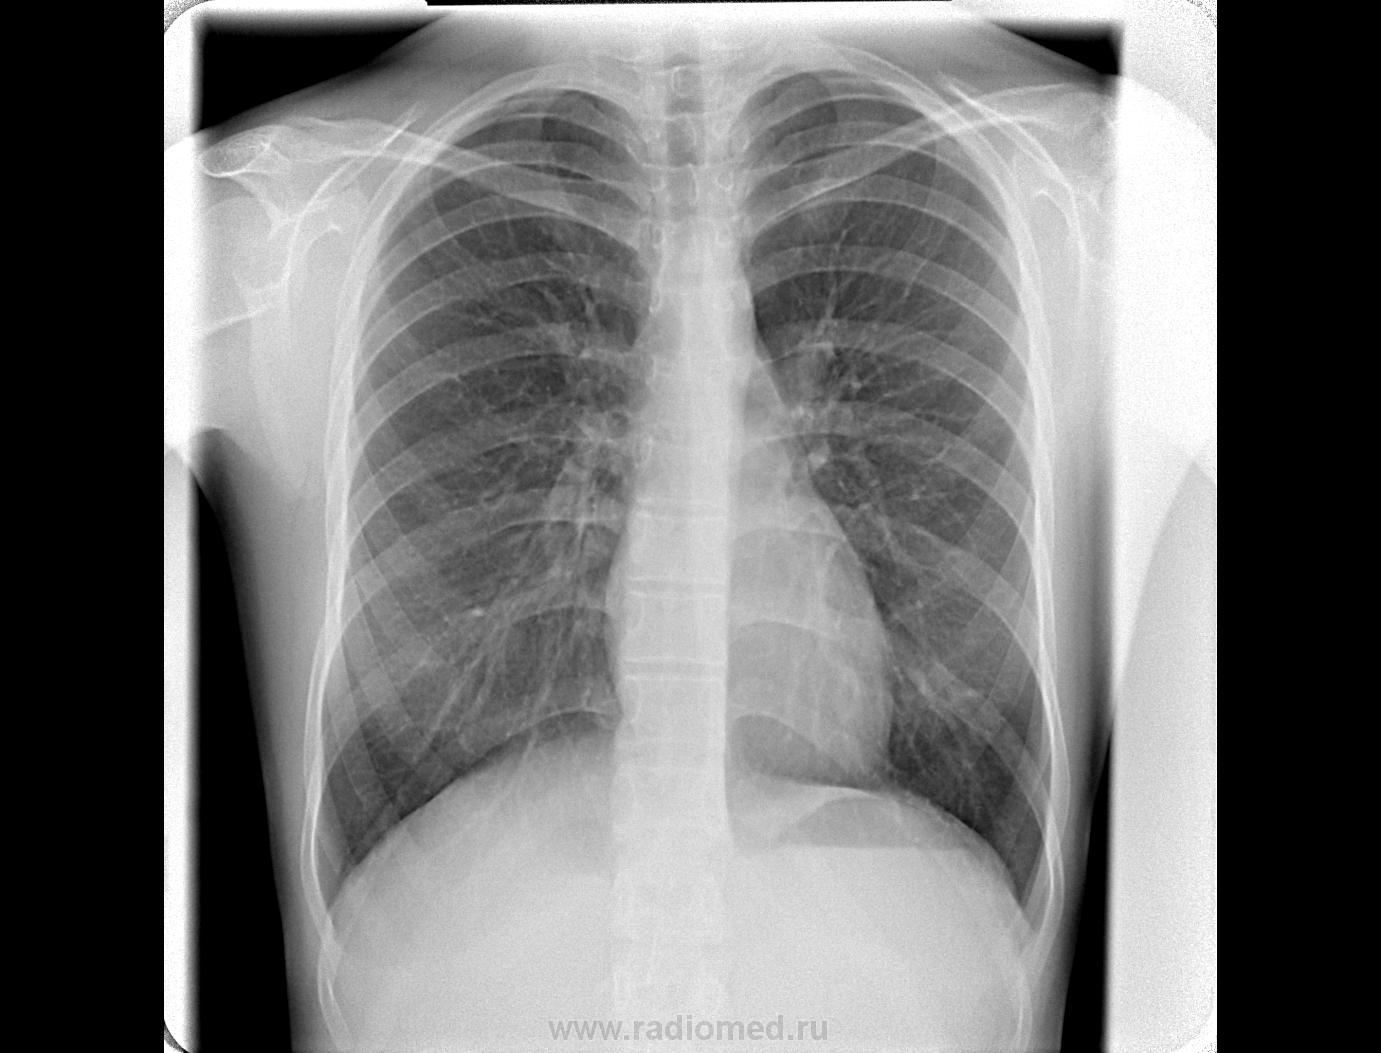

Молодая девушка 1993.г.р, обратилась с жалобами на боли в костях грудной клетки и в гр.отделе позвоночника.

Мне для себя интересно, это нашлось в результате флюорографии???? или прицельно рентген поз-ка делали???

Андрей Викторович, здравствуйте. "Дырку" нашла на рентгенограммах, а флюшку - для профилактики, т.к были боли в гр.клетке; изменения -то нашла в ТЕЛЕ Th5, а по КТ- в основании остистого отростка (суперпозиция)